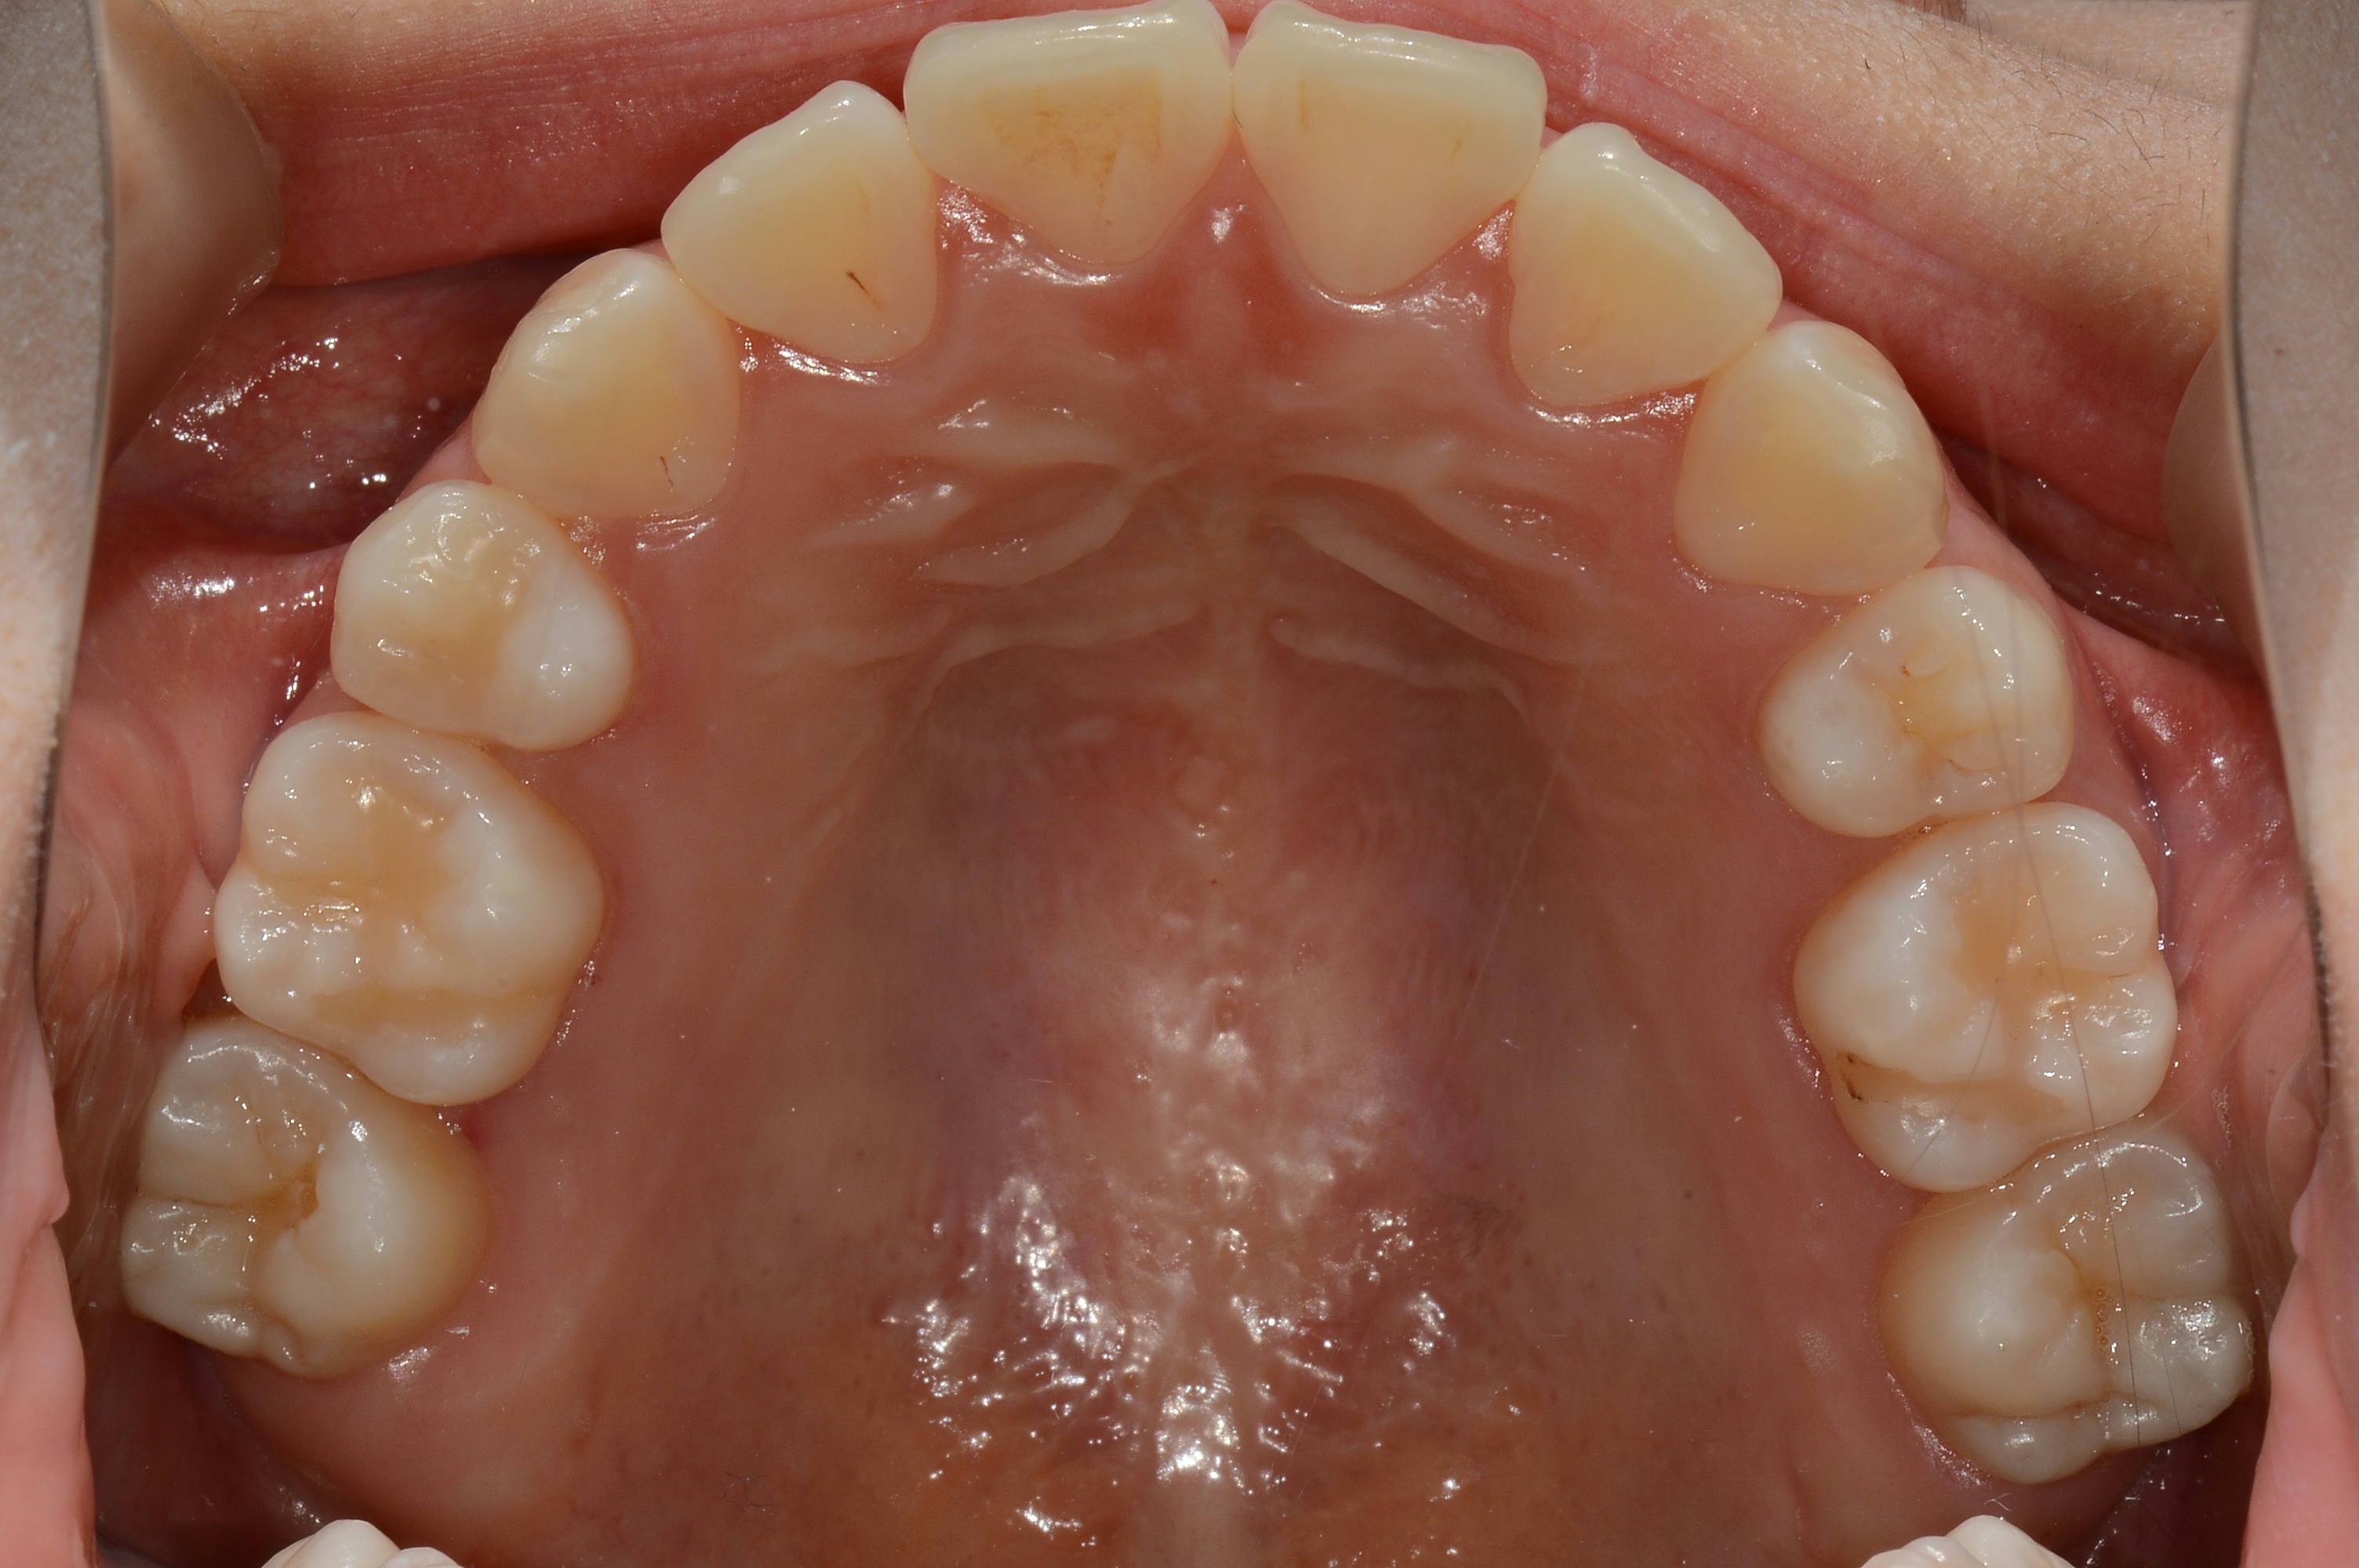

치료 후 사진입니다.